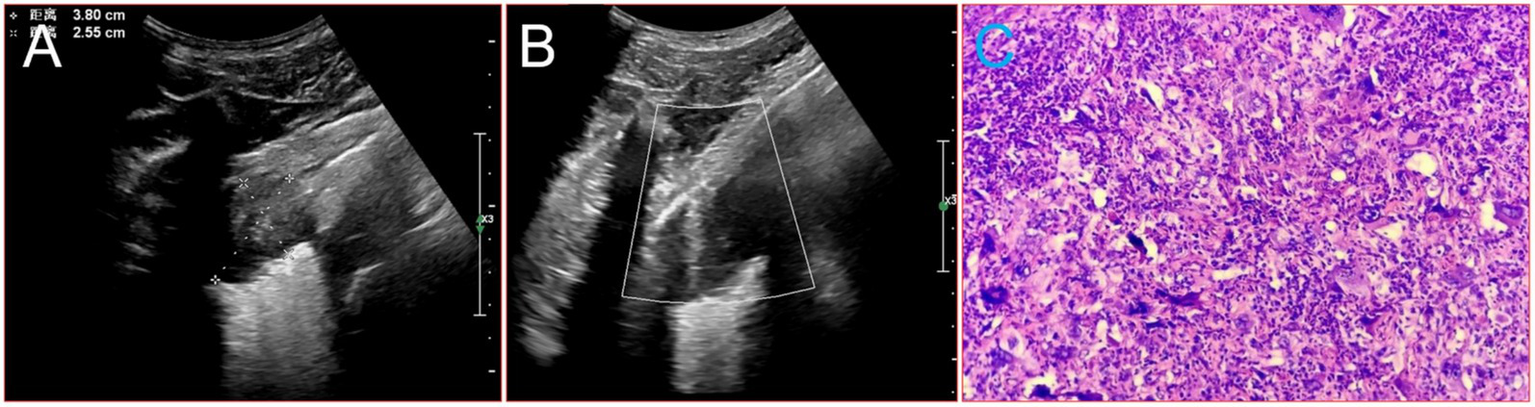

Given that the patient had no history of fever and no special abnormalities in the results of laboratory tests, the multidisciplinary team (MDT) suggested that lung metastases or lung malignancies with intrapulmonary metastasis should be considered. A magnetic resonance imaging (MRI) examination of the head was performed and revealed brain metastatic lesion (Figures 2A,B). Unfortunately, due to financial constraints, the patient did not undergo the PET-CT examination. At the same time, he underwent gastroscopy and colonoscopy because of concerns about weight loss, but no tumor was found. Finally, a puncture biopsy of the lung lesion was performed under ultrasound guidance, and the histologic results confirmed PSC with giant-cell carcinoma (Figures 3A–C), PD-L1 (=1%, Clone: 22C3, Dako, Agilent Technologies, Inc.).

Figure 3

Image about puncture biopsy of the lung lesion under ultrasound guidance, and the histologic results. (A) Ultrasound images of the lesion in the patient’s lower lobe of the left lung. (B) The process of puncture biopsy of the lung lesion under ultrasound guidance. (C) HE × 20.